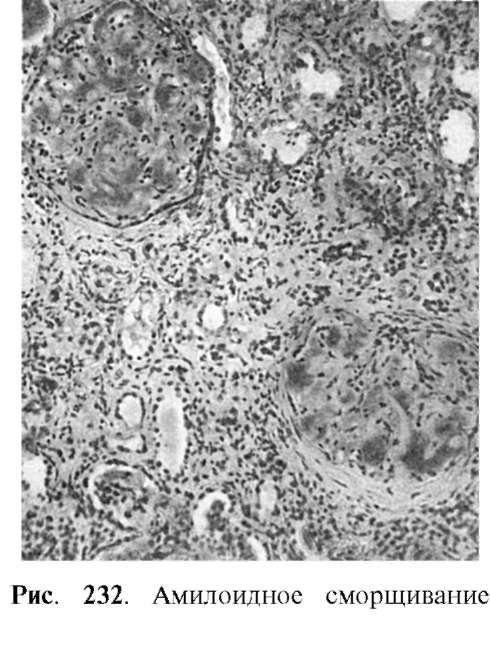

Вазотемической (уремической) стадии в связи с нарастающим амилоидозом и склерозом наблюдаются гибель большинства нефронов, их атрофия, замещение соединительной тканью. Почки обычных размеров или несколько уменьшены. Они очень плотные, со множеством рубцовых западений на поверхности (амилоидно-сморщенные почки) (рис. 232).